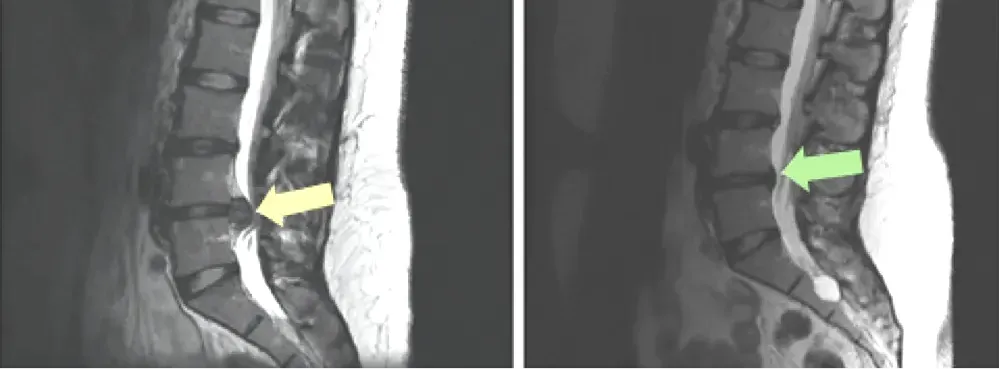

An MRI can reveal a variety of conditions that may be causing sciatica. For example, a herniated disc, which occurs when the soft center of a spinal disc pushes through a crack in the tougher exterior casing, is a common cause of sciatic nerve pain.

An MRI can also show spinal stenosis, a narrowing of the spinal canal that compresses the nerves. Other detectable conditions include spondylolisthesis (slipped disc), degenerative disc disease, and in rare cases, tumors or infections.